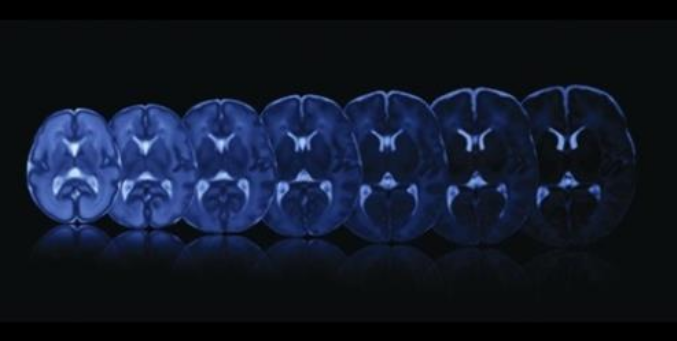

Nuevas técnicas para el estudio de la maduración del cerebro durante el embarazo